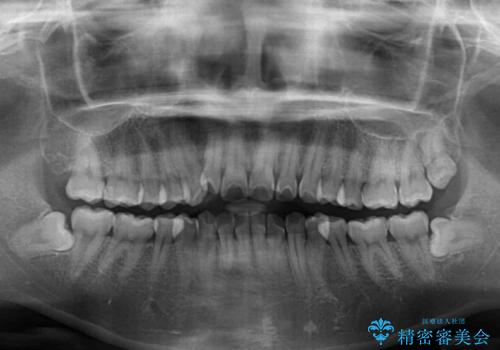

- 上下前歯のデコボコを気にして来院された患者様です。

インビザラインによる上下歯列の拡大と、IPR(歯と歯の間を削る)にるスペースの獲得により、前歯のデコボコを改善することとしました。